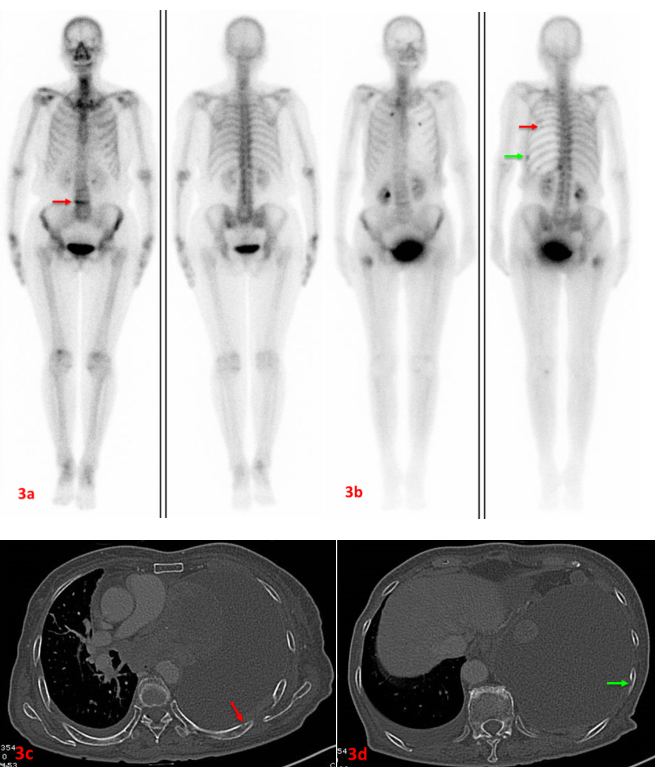

老年女性,左肺腺癌。初次ECT(3a圖)示L4(3a紅箭)代謝異常增強,考慮壓縮性骨折。7個月后復查ECT(3b圖)示雙側多根肋骨、右側股骨上端代謝異常增強,考慮多發骨轉移。L4代謝較前片明顯減低。同期CT檢查可見左側第7后肋(3c紅箭)、左側第9后肋(3d綠箭)溶骨性破壞。此病例證實了ECT定期復查的必要性,建議惡性腫瘤患者3-6個月復查一次。